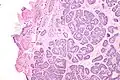

Micrograph of a Sertoli cell nodule. H&E stain. | |

Sertoli cell nodules are unencapsulated nodules that consist of:[2][3][4]

- cells arranged in well-formed tubules (that vaguely resemble immature Sertoli cells), with

- bland hyperchromatic oval/round nuclei that are stratified, and

- may contain eosinophilic (hyaline) blob in lumen (centre).